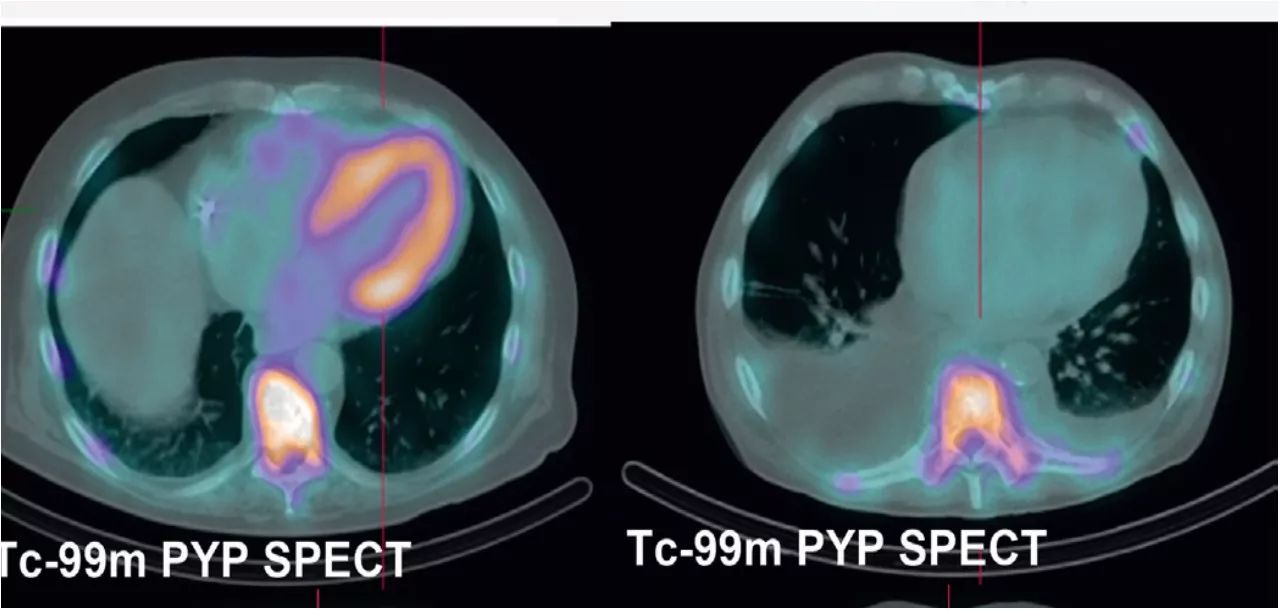

TC-99m PYP、SPECT:ATTR型心肌摄取;AL型心肌不摄取

ATTR型淀粉样变 AL型淀粉样变

一旦诊断CA,需进行分型, TC-99m PYP SPECT,可确定ATTR型,排除AL型